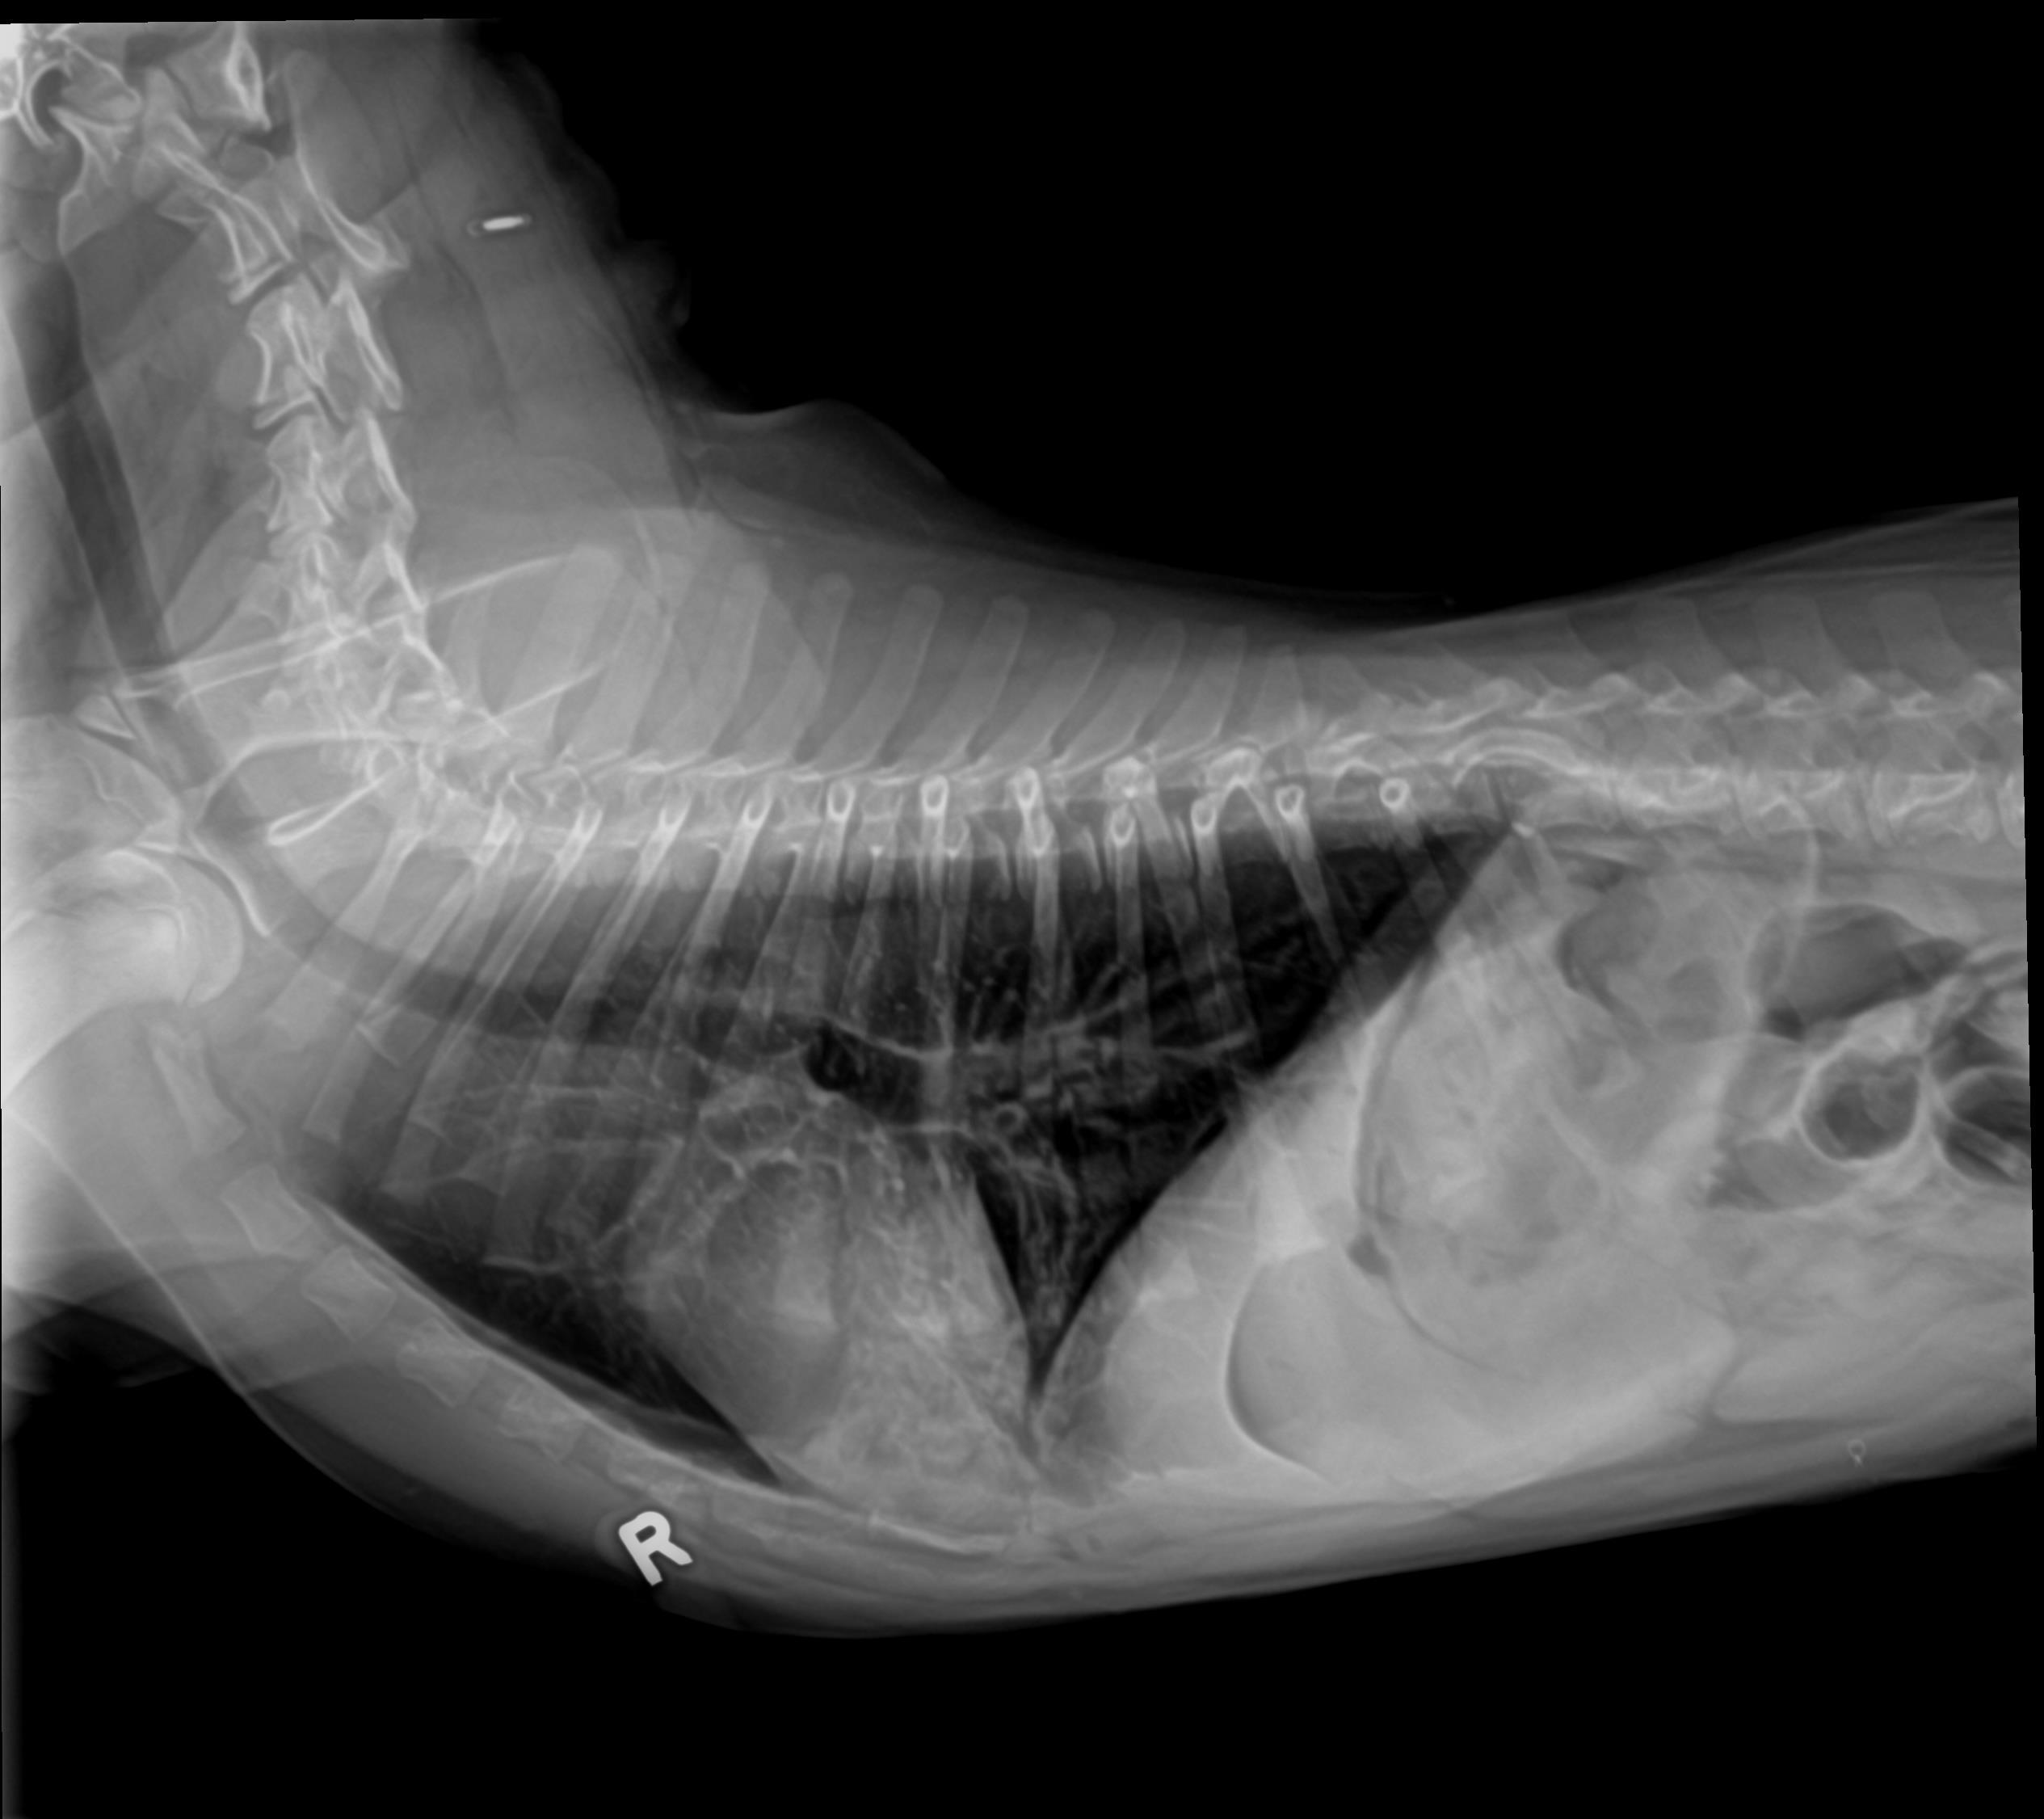

Physical exam findings and radiographs consistent with pneumonia.

Patient’s appetite and energy returned two days after starting additional therapy. Repeat radiographs at post-five days showed significant improvement as well.

Radiographs Before Treatments